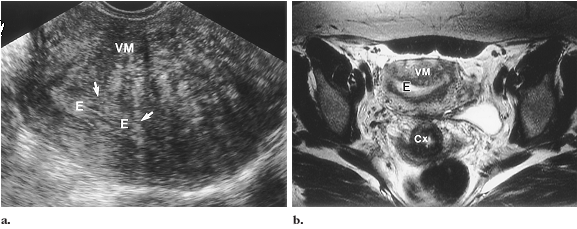

Siêu âm đầu dò âm đạo: thường gặp nhất là vùng giảm âm hay không đồng nhất của lớp cơ không rõ ranh giới, không gây hiệu ứng khối, có thể thấy những ổ dịch nhỏ (50% BN) do giãn nang tuyến hay chẩy máu thường < 5mm. sự dầy lên của lớp cơ tạo hình ảnh lệch tâm của buồng nội mạc,

MRI: chuỗi xung T2W, sự dầy lên của lớp cơ hay vùng chuyển tiếp (juntion zone) (bình thường 7-8mm có thể tới 12mm), kết hợp với những ổ tăng tín hiệu dạng dịch để xác đinh chẩn đoán

![]() |

| Lạc nội mạc tử cung trong cơ MRI tiểu khung |